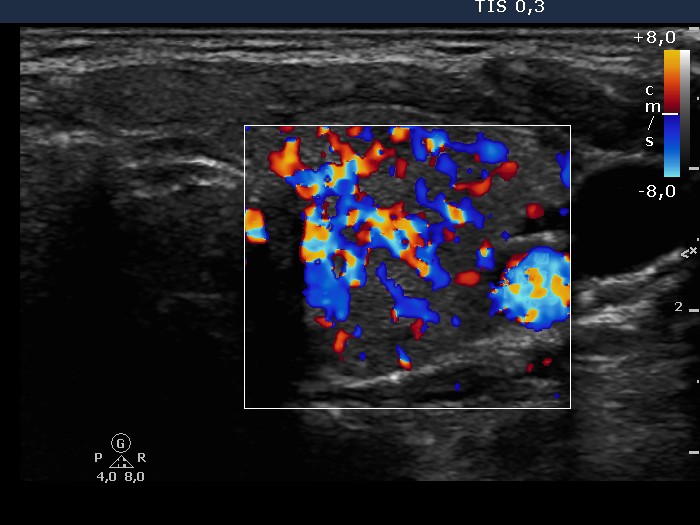

Follow-up investigation 32 months after first visit (ultrasonographic picture 5)

Patient 14 months after discontinuation of thyrostatic therapy in hyperthyroid state

Left lobe, transverse scan. The vascularization is significantly increased.